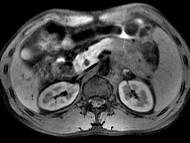

问题 男45岁、腹部胀痛不适、胃纳减退、体重减轻、中腹部可触肿块,影像检查如图,应诊断为()

选项 A.急性胰腺炎 B.慢性胰腺炎 C.胰腺体尾部癌 D.胰岛细胞瘤 E.腹膜后淋巴结结核

答案 C